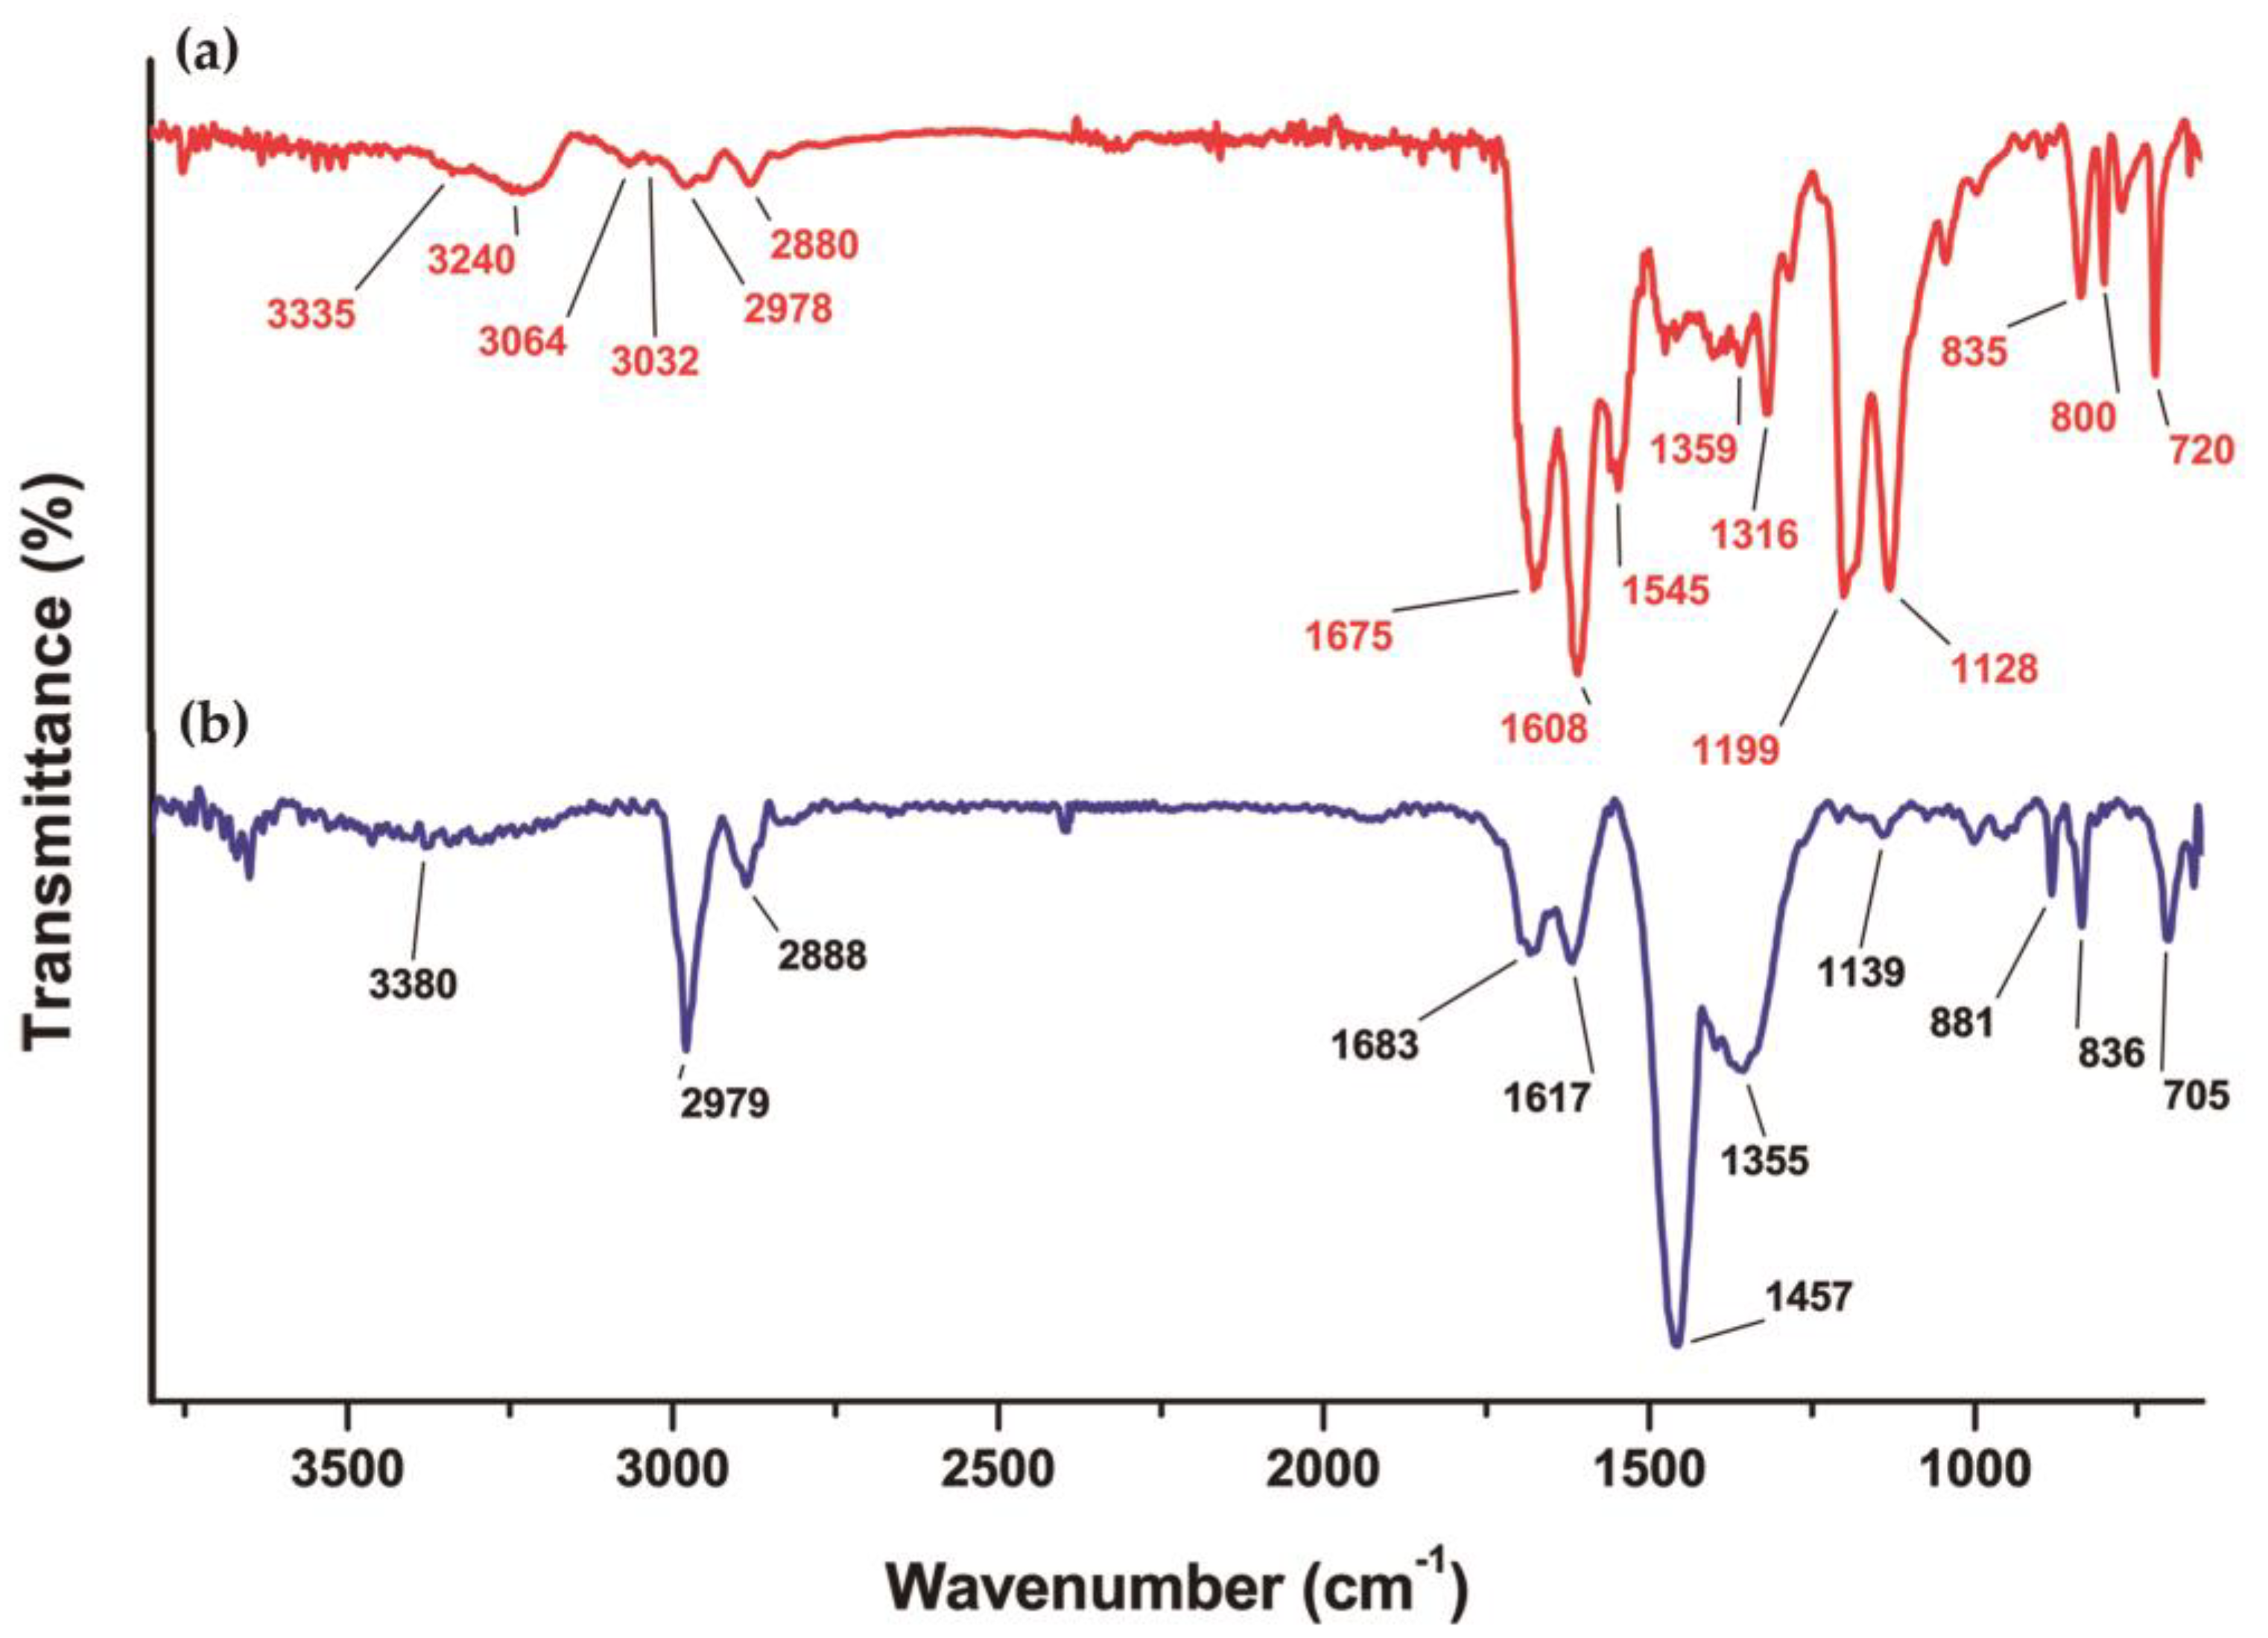

3.3. Chemical Evaluation

3.3.1. DOTA-iFAP